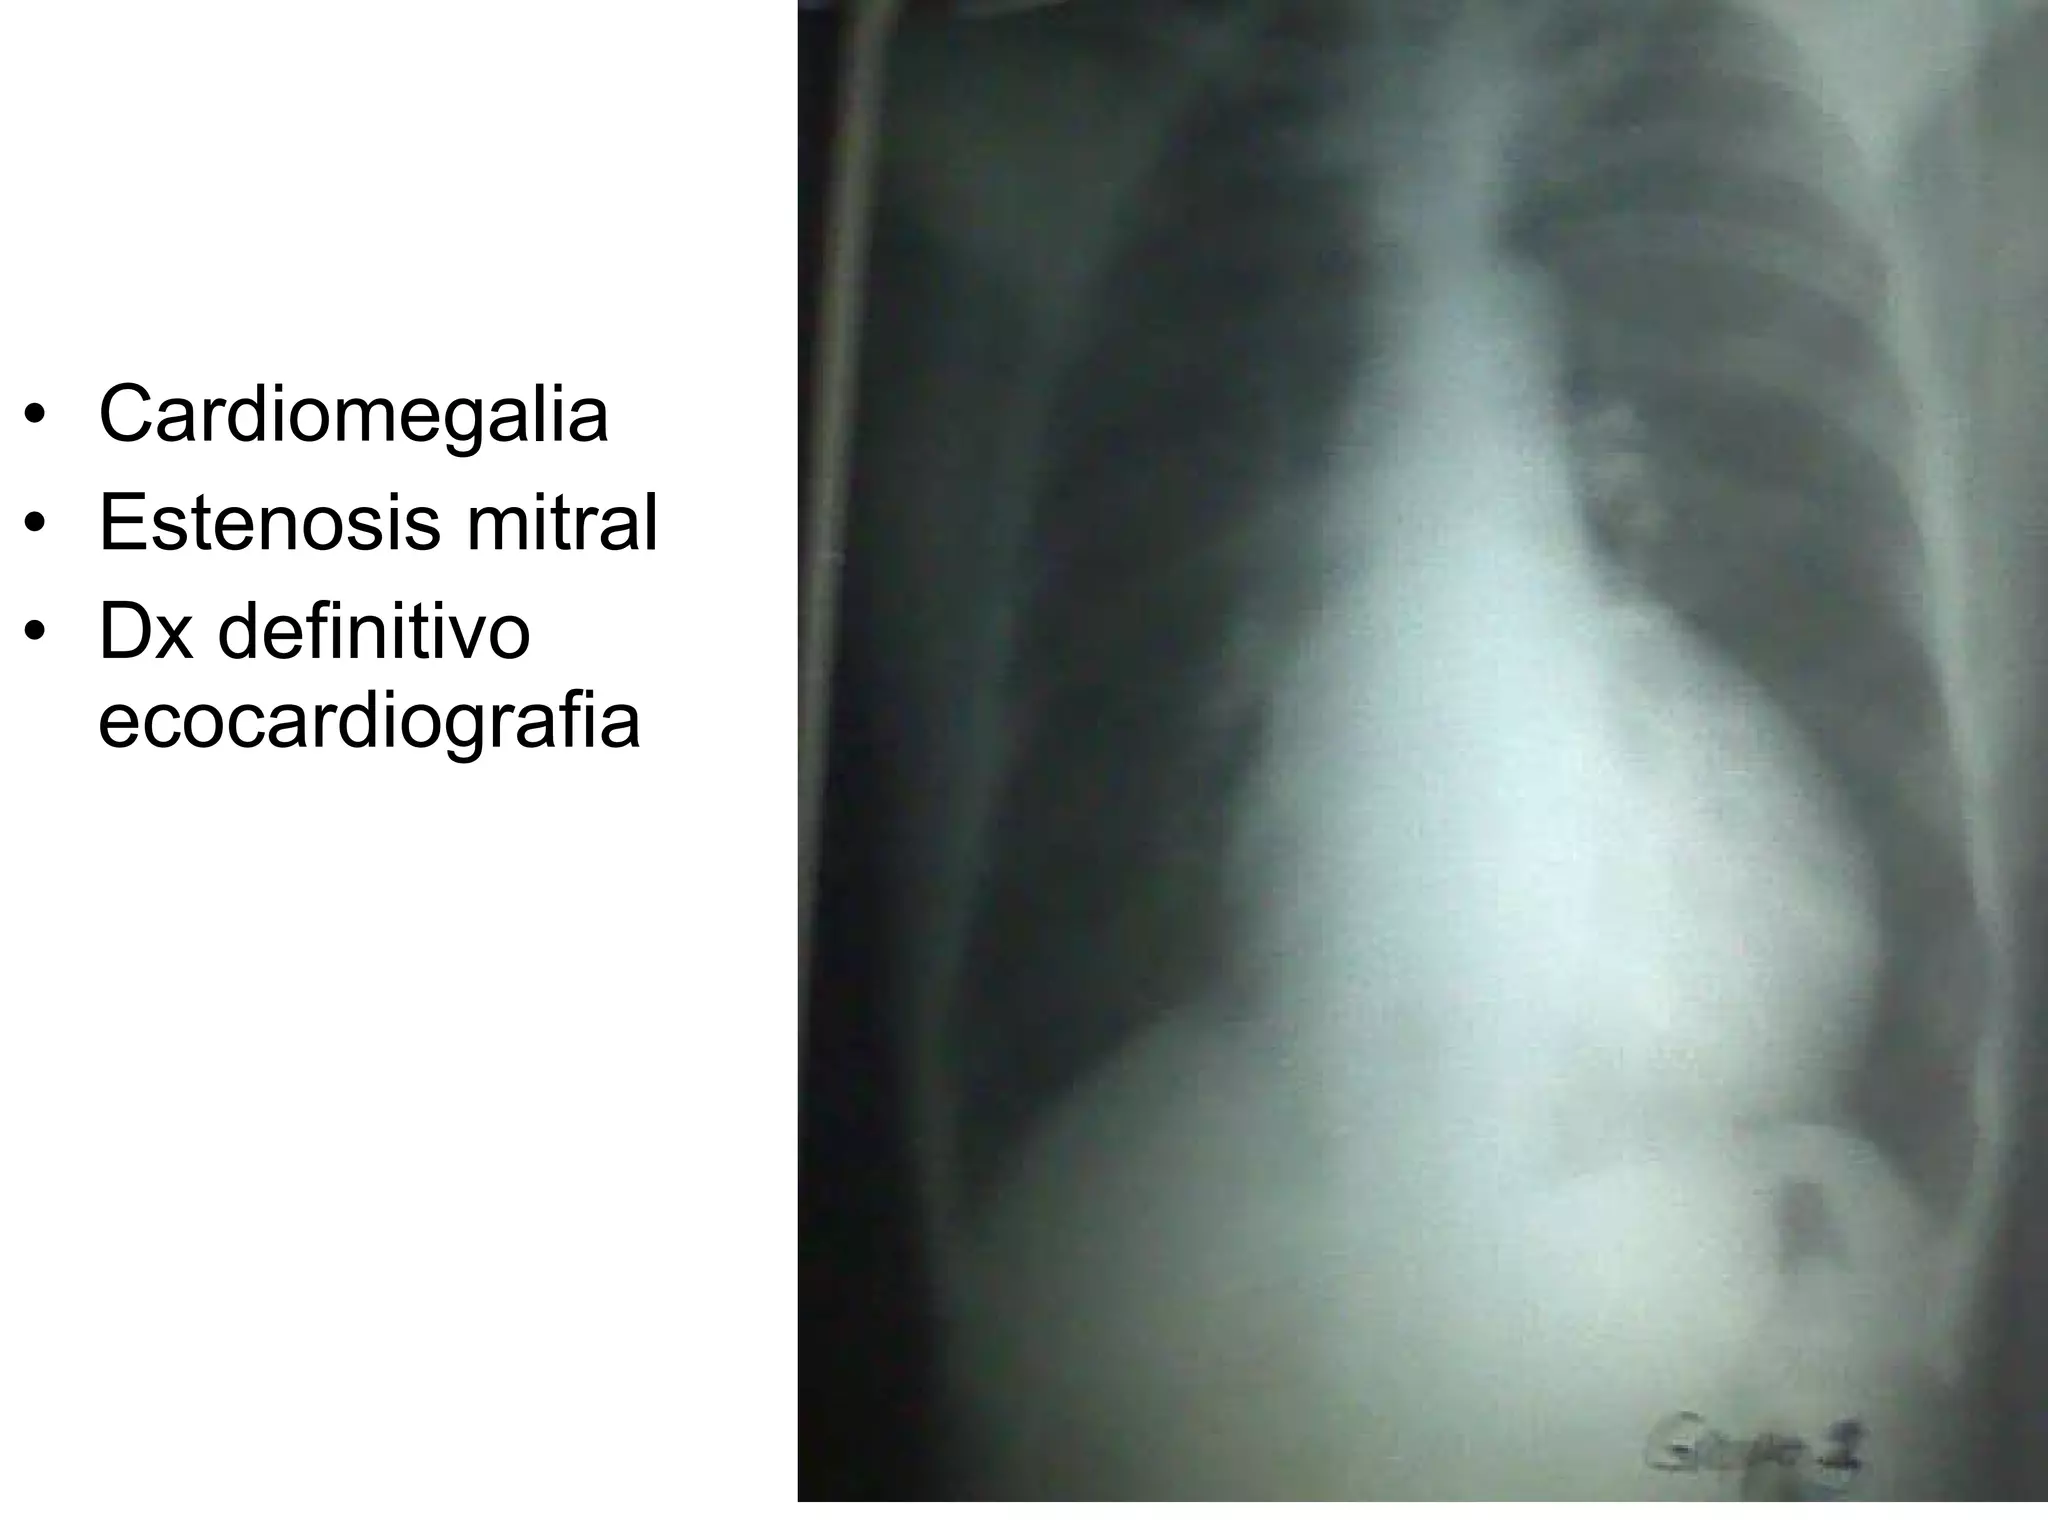

Cardiomegalia Estenosis mitral Dx definitivo ecocardiografia